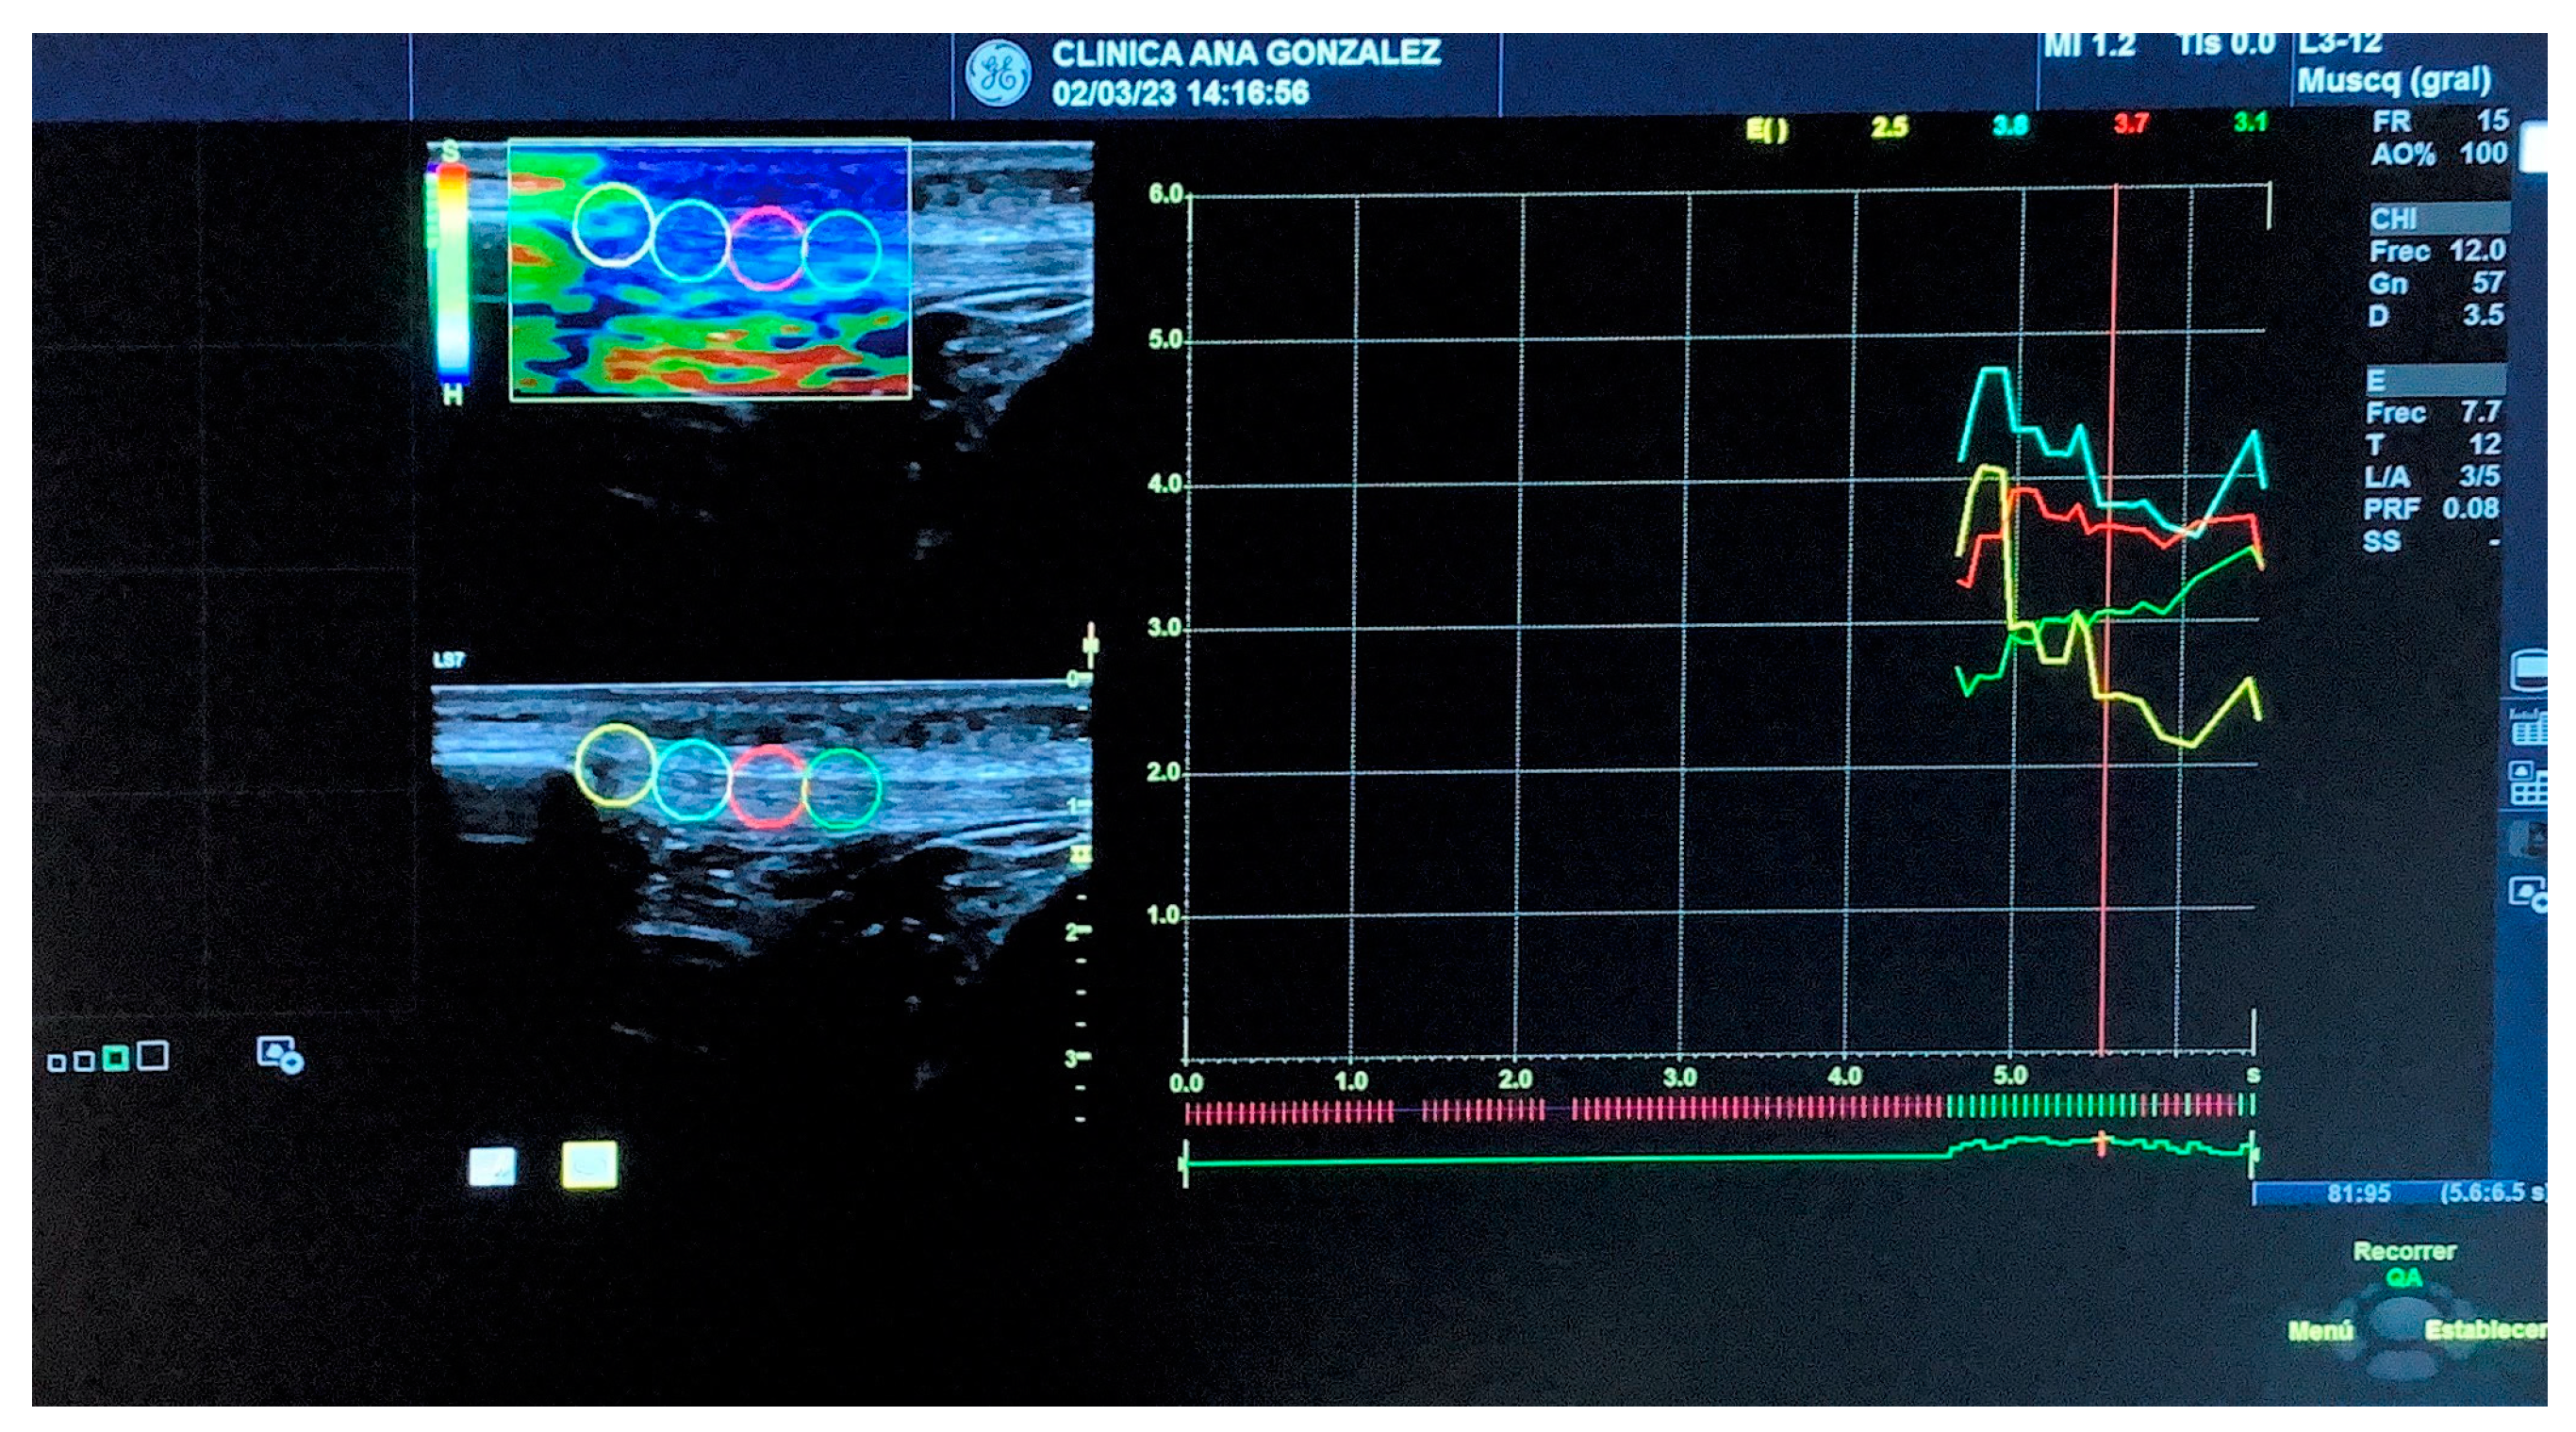

A physiotherapist with 12 years of experience in musculoskeletal ultrasound imaging and 4 years of experience in SEL used a Logiq S7 with a 15 MHz linear probe (GE Healthcare, Milwaukee, WI, USA) to carry out all measurements. The evaluator carried out a protocol study before the research started, presenting an excellent ICC (>0.9). The measurements were performed following recommendations from previous studies [24,25] and with the patient lying supine with the knee flexed at 30 degrees. The patellar tendon was located using the kneecap as the upper border and the tuberosity of the tibia as the lower border [24]. The selected image featured 5 green bars, with this indicating the highest level of quality recommended by the inbuilt software in the computer [19,24]. Four circular 5 mm regions, which ranged from the kneecap to the tibial tuberosity, were used to calculate the SEL value along the patellar tendon (see Figure 2). The values shown ranged from 0 to 6, from the softest to the hardest [19].

Figure 2. Patellar Tendon SEL measurements. Note. From left to right: Point 1: insertion of the PT to the kneecap (yellow); Point 2: body of the tendon in its med-proximal portion (blue); Point 3: body of the tendon in its mid portion (red); Point 4: body of the tendon in its mid-distal portion (green).